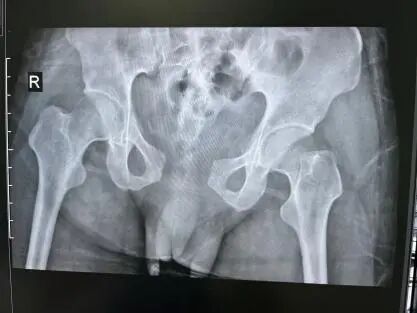

经过X线、CT等系统检查,李先生被诊断为骨盆骨折(耻骨支骨折、耻骨联合分离、骶髂关节分离)。这类骨盆前后环骨折属于不稳定骨折,首选手术治疗。然而,传统开放手术需要广泛的剥离软组织,充分显露骨折处,给予骨折复位和固定。切开复位内固定手术会带来创伤大、失血多、切口愈合慢、瘢痕影响美观等问题。同时大切口也会增加神经、血管损伤及切口感染的风险。

术前CR